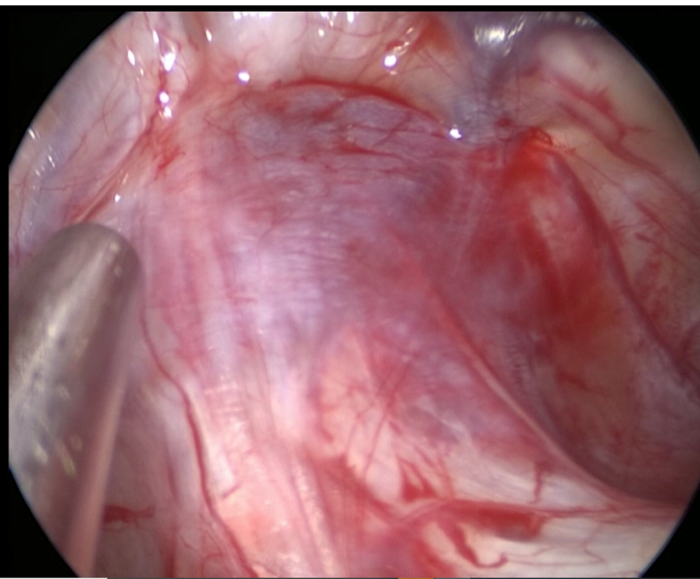

调整内镜角度,发现骶管囊肿病因所在--------硬膜囊与囊肿之间的漏口(如下图示)